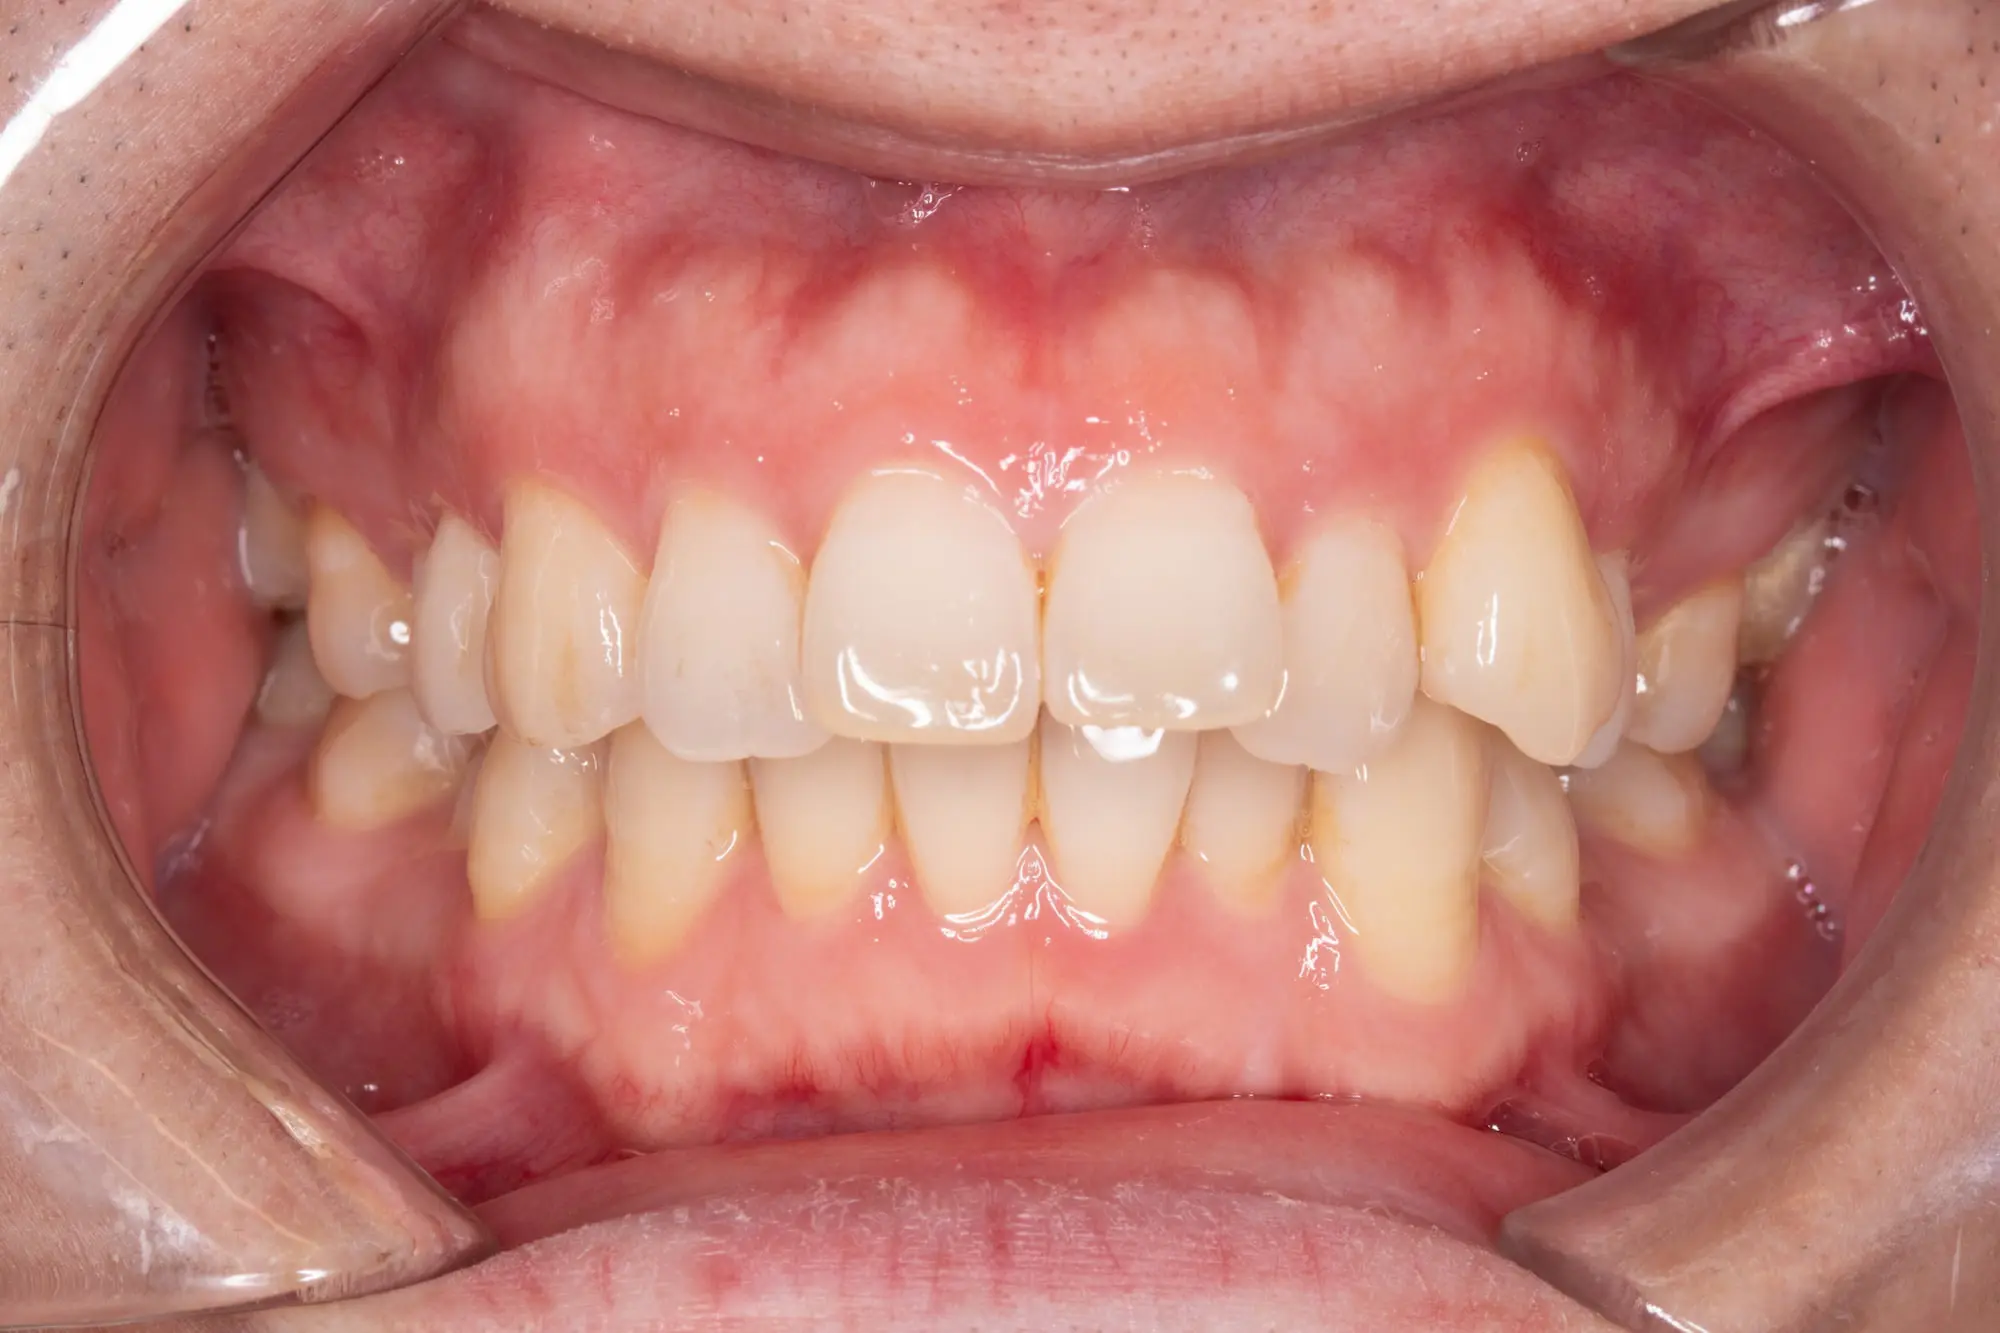

Crossbite/Uneven Bite

Before

After